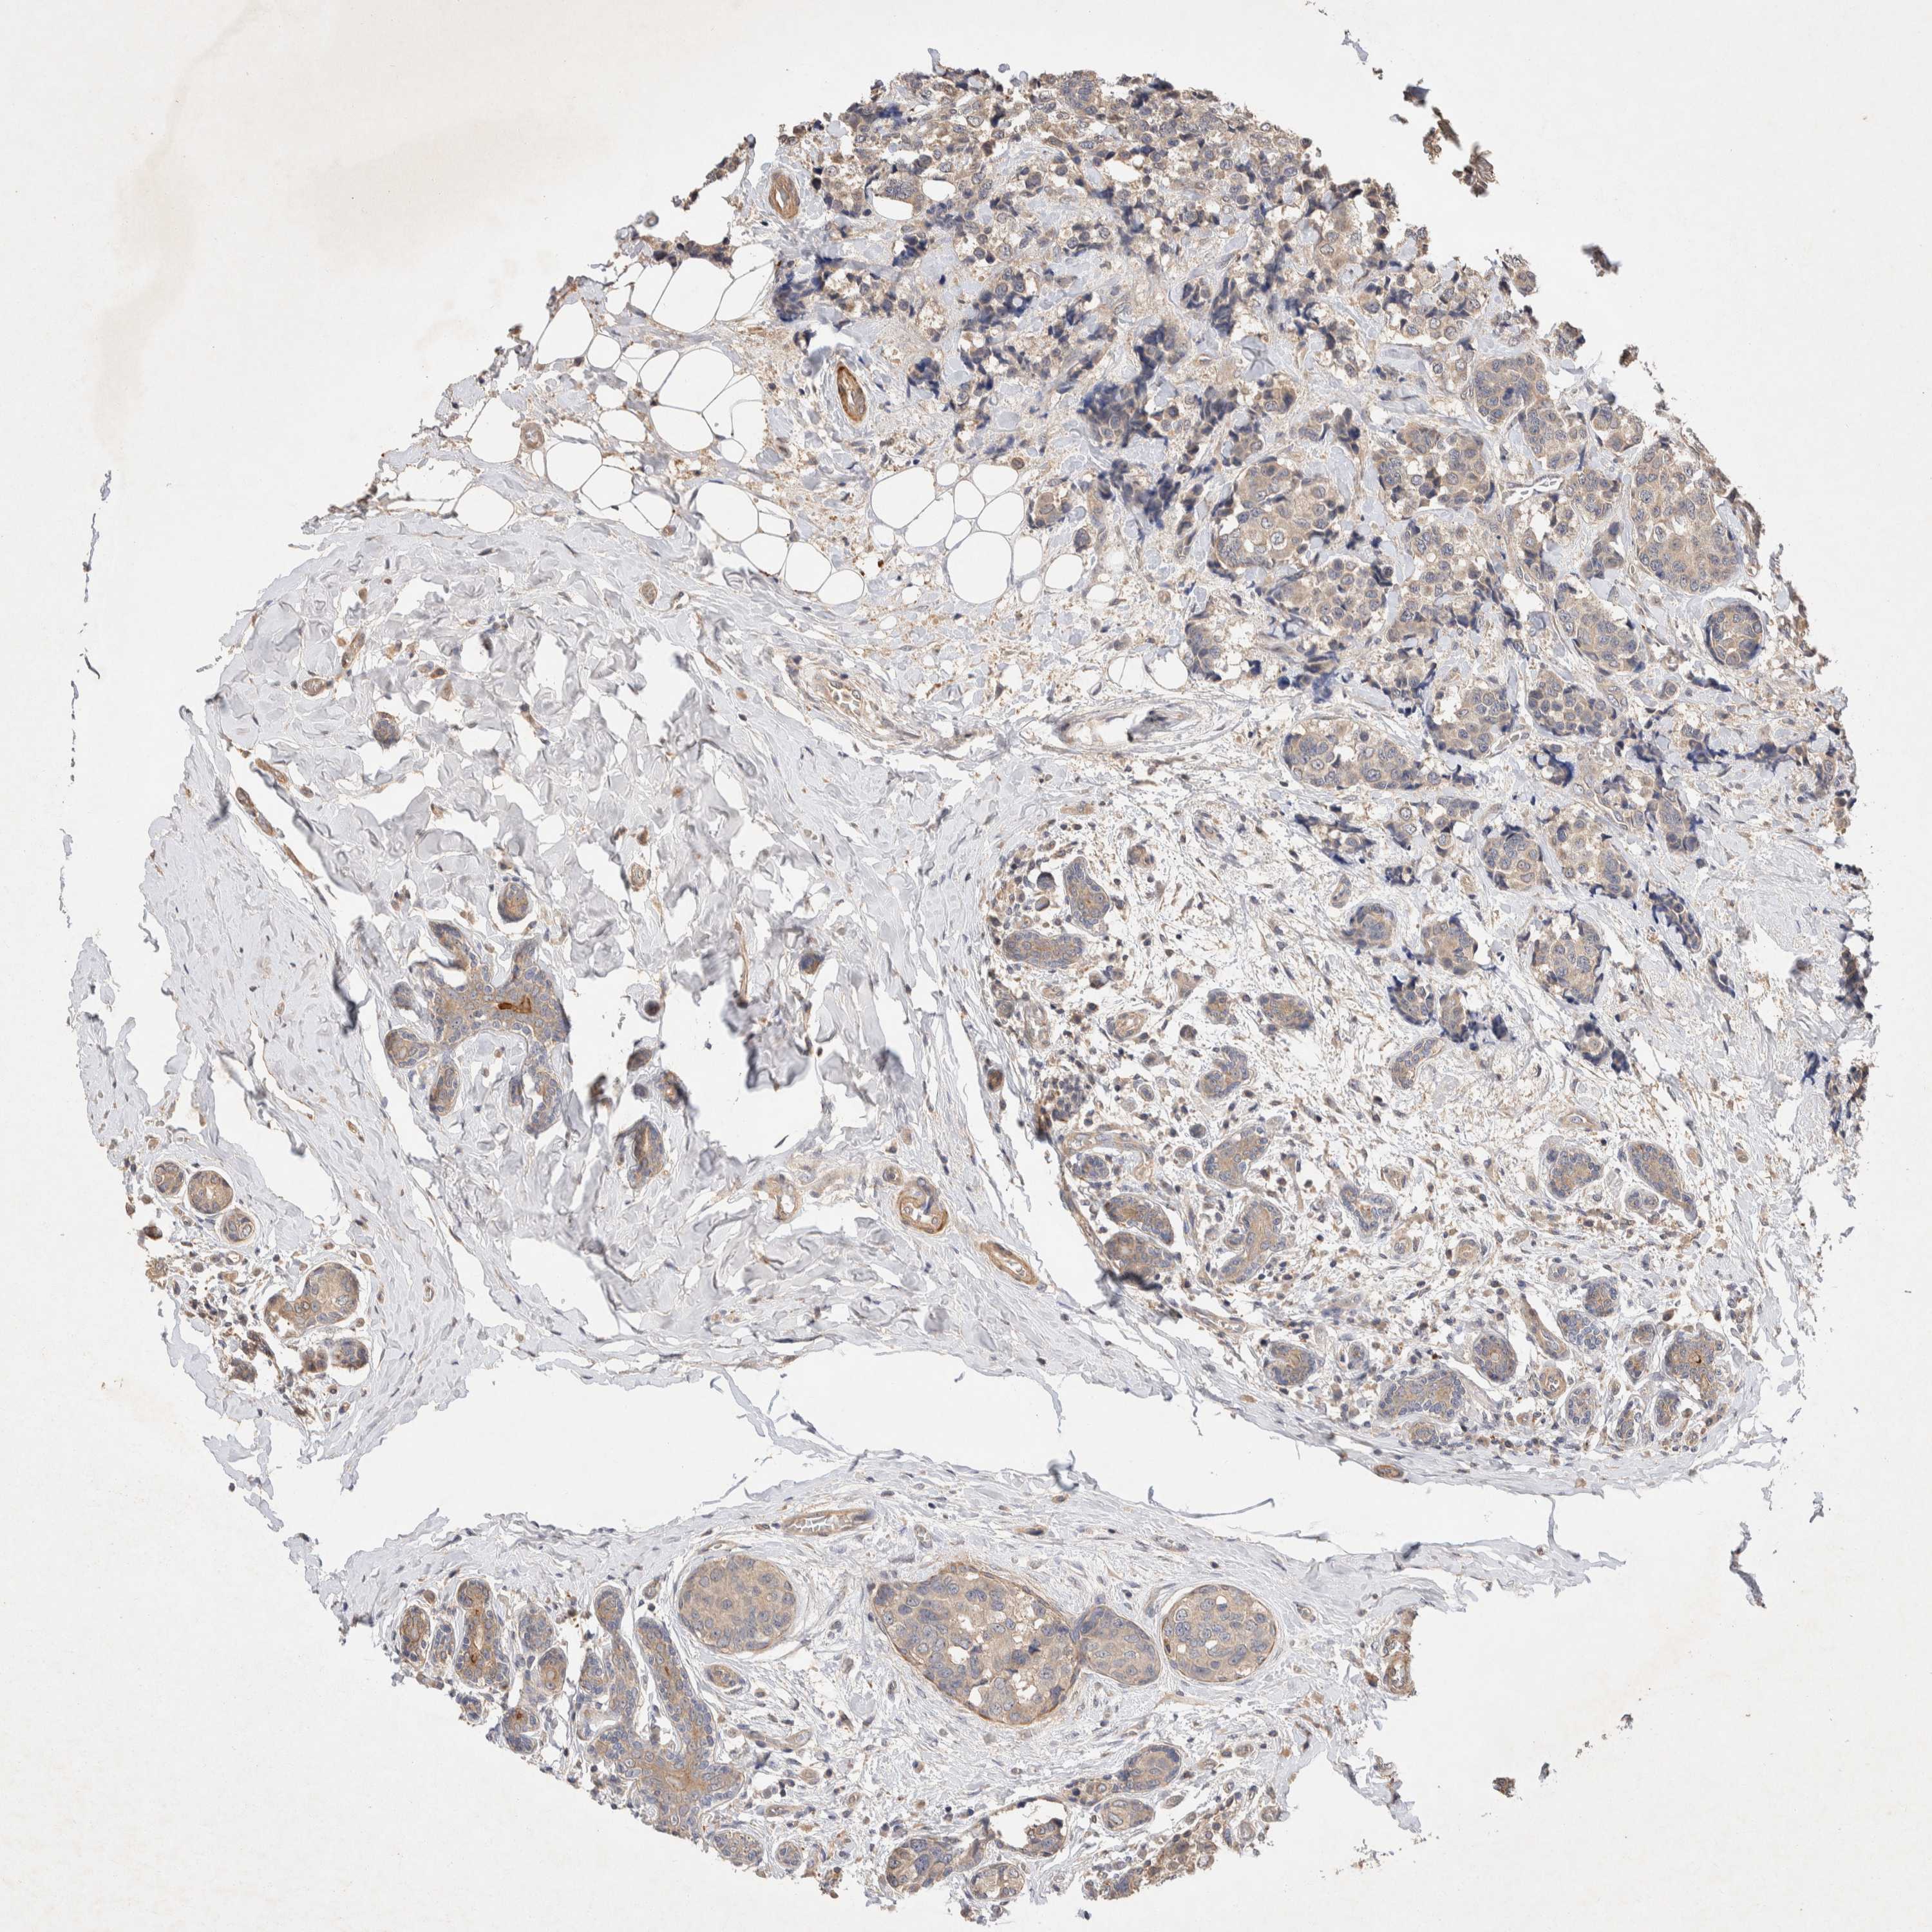

CANCER BREAST CANCER Show tissue menu

BRCA TCGA BRCA VALIDATION PROTEIN EXPRESSION

NSMAF is not prognostic in Breast Invasive Carcinoma (TCGA)